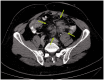

A polyp is defined as any mass protruding into the lumen of a hollow viscus. Colorectal polyps may be classified by their macroscopic appearance as sessile (flat, arising directly from the mucosal layer) or pedunculated (extending from the mucosa through a fibrovascular stalk). Colorectal polyps may also be histologically classified as neoplastic or as non-neoplastic (hyperplastic, hamartomatous, or inflammatory). The neoplastic polyps are of primary importance because they harbor a malignant potential, which represents a stage in the development of colorectal cancer. For this reason, it is essential to identify these polyps at a sufficiently early stage, when a simple outpatient procedure to remove them can interrupt the development of colorectal cancer and prevent disease and death. When invasive carcinoma arises in a polyp, careful consideration must be given to ensuring the adequacy of treatment. Although most neoplastic polyps do not evolve into cancer, it is well accepted that the majority of colorectal carcinomas evolve from adenomatous polyps; the sequence of events leading to this transformation is referred to as the adenoma-to-carcinoma sequence. The presence of a systemic process that promotes the development of multiple gastro-intestinal polyps is termed 'polyposis'. Hereditary gastro-intestinal polyposis syndromes account for approximately 1% of all cases of colorectal cancer and are associated with a broad spectrum of extra-colonic tumors. Early detection and accurate classification of these syndromes are essential, in order to initiate a surveillance program for the early detection of cancer. Several polyposis syndromes have been described, each having its own genetic basis and characteristic polyp distribution, clinical presentation, and malignancy risk. Diagnostic modalities and treatment options for neoplastic polyps-as well as the most prevalent polyposis syndromes-are reviewed below.